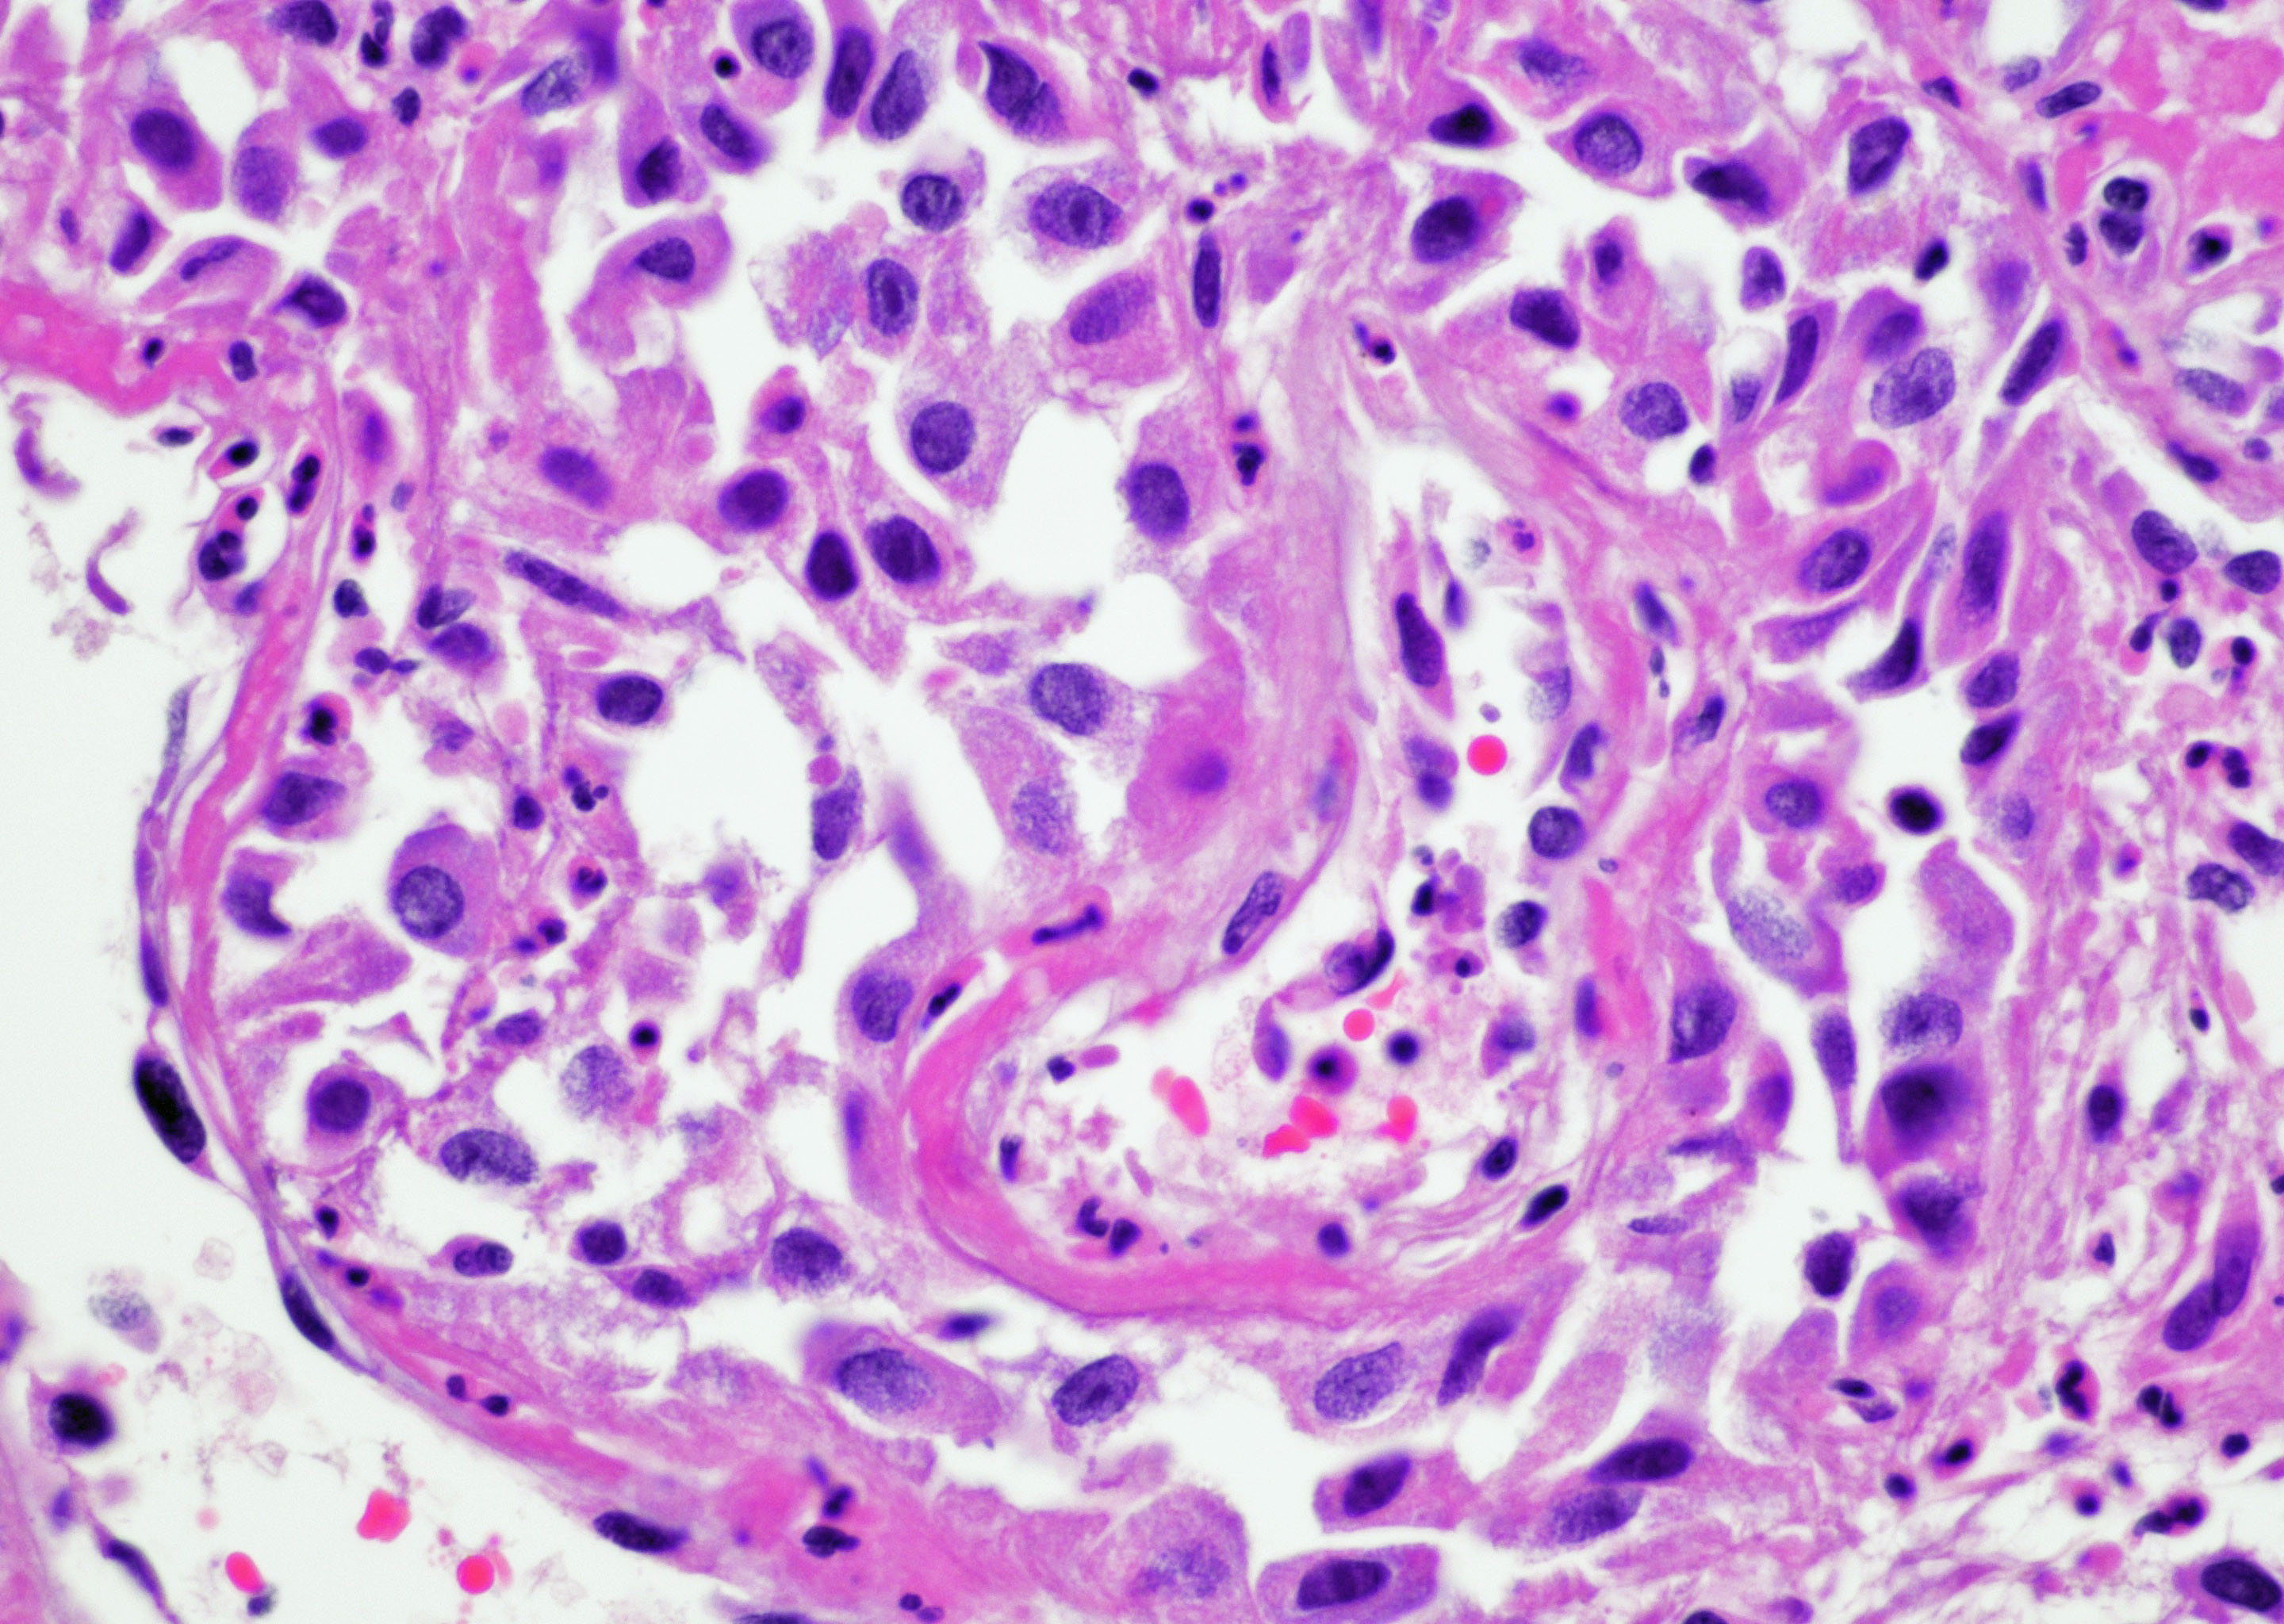

- Vessels with fibrin thrombi, fibrinoid vascular necrosis, vascular congestion, thickened walls, endothelial proliferation and telangiectasia

- Reactive multinucleated stromal fibroblasts with smudgy nuclei

- Fibrosis and edema

- Hemorrhage and hemosiderin

- Pseudocarcinomatous urothelial hyperplasia: variable sized urothelial cords and nests with rounded or irregular edges present in the lamina propria and enclose dilated blood vessels with fibrin deposition (Am J Surg Pathol 2008;32:92)

- Acute phase: edematous, congested and telangiectatic vessels, acute and chronic inflammatory infiltrate, atypical stromal cells with multinucleated forms

Microscopic (histologic) images

Contributed by Y. Albert Yeh, M.D., Ph.D. and Jennifer Lee, M.D.